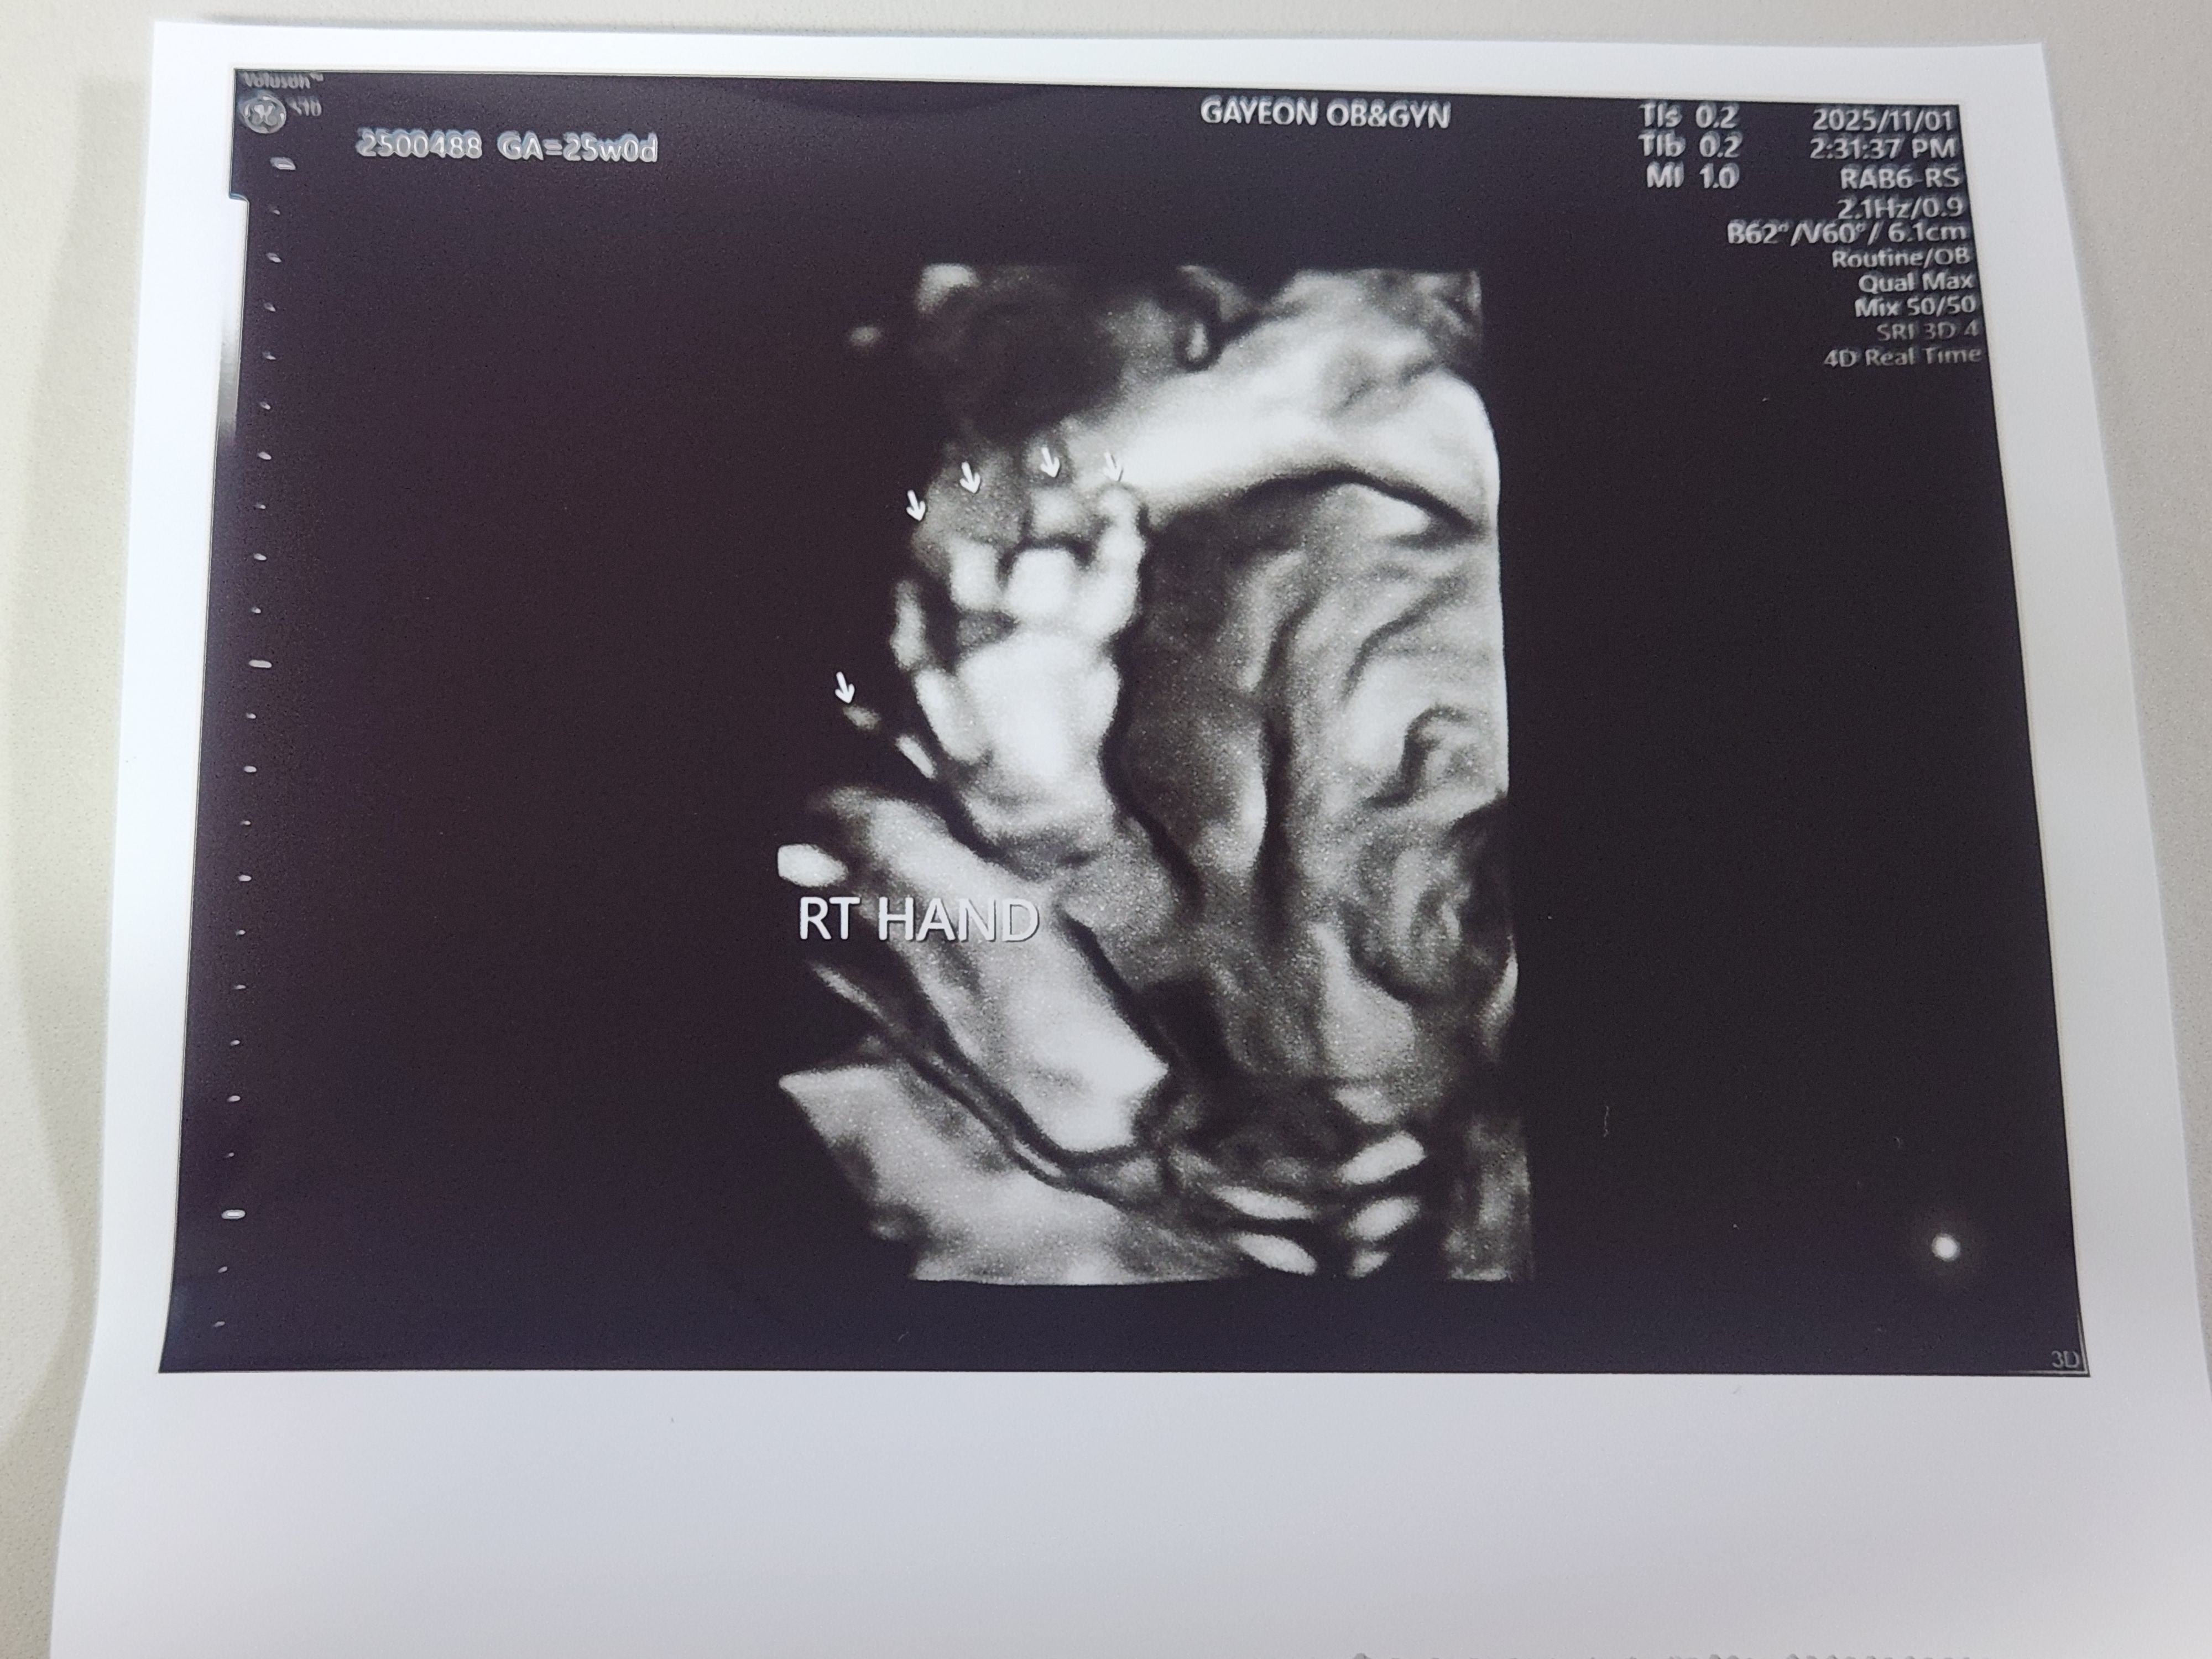

왼쪽 오른쪽 손가락입니다.

입체초음파시 아기가 손을 올리고 있어서 사진이 잘 찍힐까 걱정했는데, 선생님께서 배를 흔들며 아기의 자세를 바꿔주셔서 얼굴을 잘 찍어주셨습니다.

저희 아기는 항상 손을 올리고 있어서, 정기진료 초음파 때도 얼굴이 항상 반이 가려져 있었는데, 전체적으로 너무 잘 보였습니다.

입체초음파에서 아기가 손을 올리고 있긴 하지만, 얼굴을 잘 캐치해서 찍어주셨습니다.